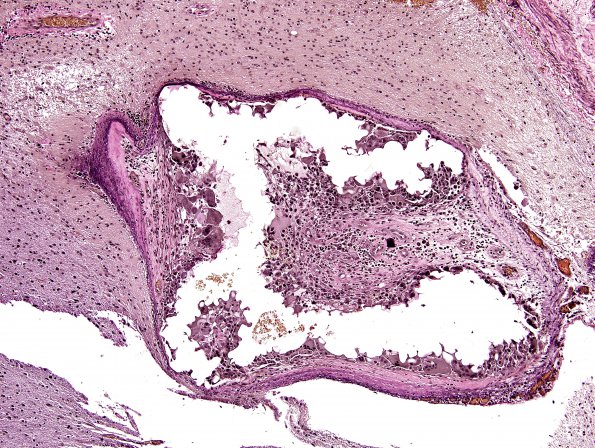

Washington University Experience | VASCULAR | AVM | 26C3 AVM (Case 26) VVG 2 embolized

26C3 AVM (Case 26) VVG 2 embolized

Higher magnification of image #26C1 (VVG)